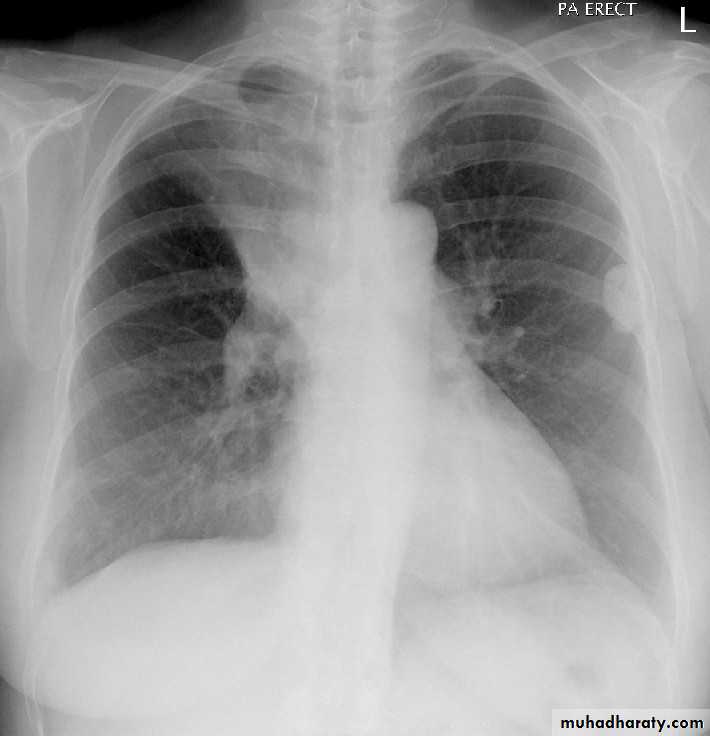

Pleural effusion

50.pleural effusion

51.pleural effusion .